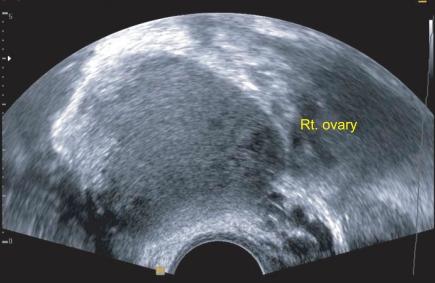

Minimally invasive surgery is widely used in benign gynecologic diseases and may be used in malignancies. We performed a single-port access laparoscopy staging - bilateral salpingo-oophorectomy, laparoscopy-assisted vaginal hysterectomy, bilateral pelvic lymphadenectomy, infracolic omentectomy, and washing cytology - in a borderline ovarian tumor. The number of harvested pelvic lymph nodes were twenty-three and there were no intraoperative or postoperative complications. Single-port access laparoscopic staging may be performed in selected patients. The efficacy, safety, and potential benefits of this technique should be evaluated in further trials.

微创手术广泛应用于良性妇科疾病,也可能应用于恶性肿瘤。我们对 1 例交界性卵巢肿瘤患者实施了经脐单孔腹腔镜分期手术(双侧输卵管卵巢切除术、腹腔镜辅助阴式子宫切除术、双侧盆腔淋巴结清扫术、大网膜切除术和腹腔冲洗细胞学检查)。共清扫盆腔淋巴结 23 枚,无术中及术后并发症。经脐单孔腹腔镜分期手术可适用于某些特定患者。该技术的疗效、安全性及潜在获益尚需进一步临床试验来评估。